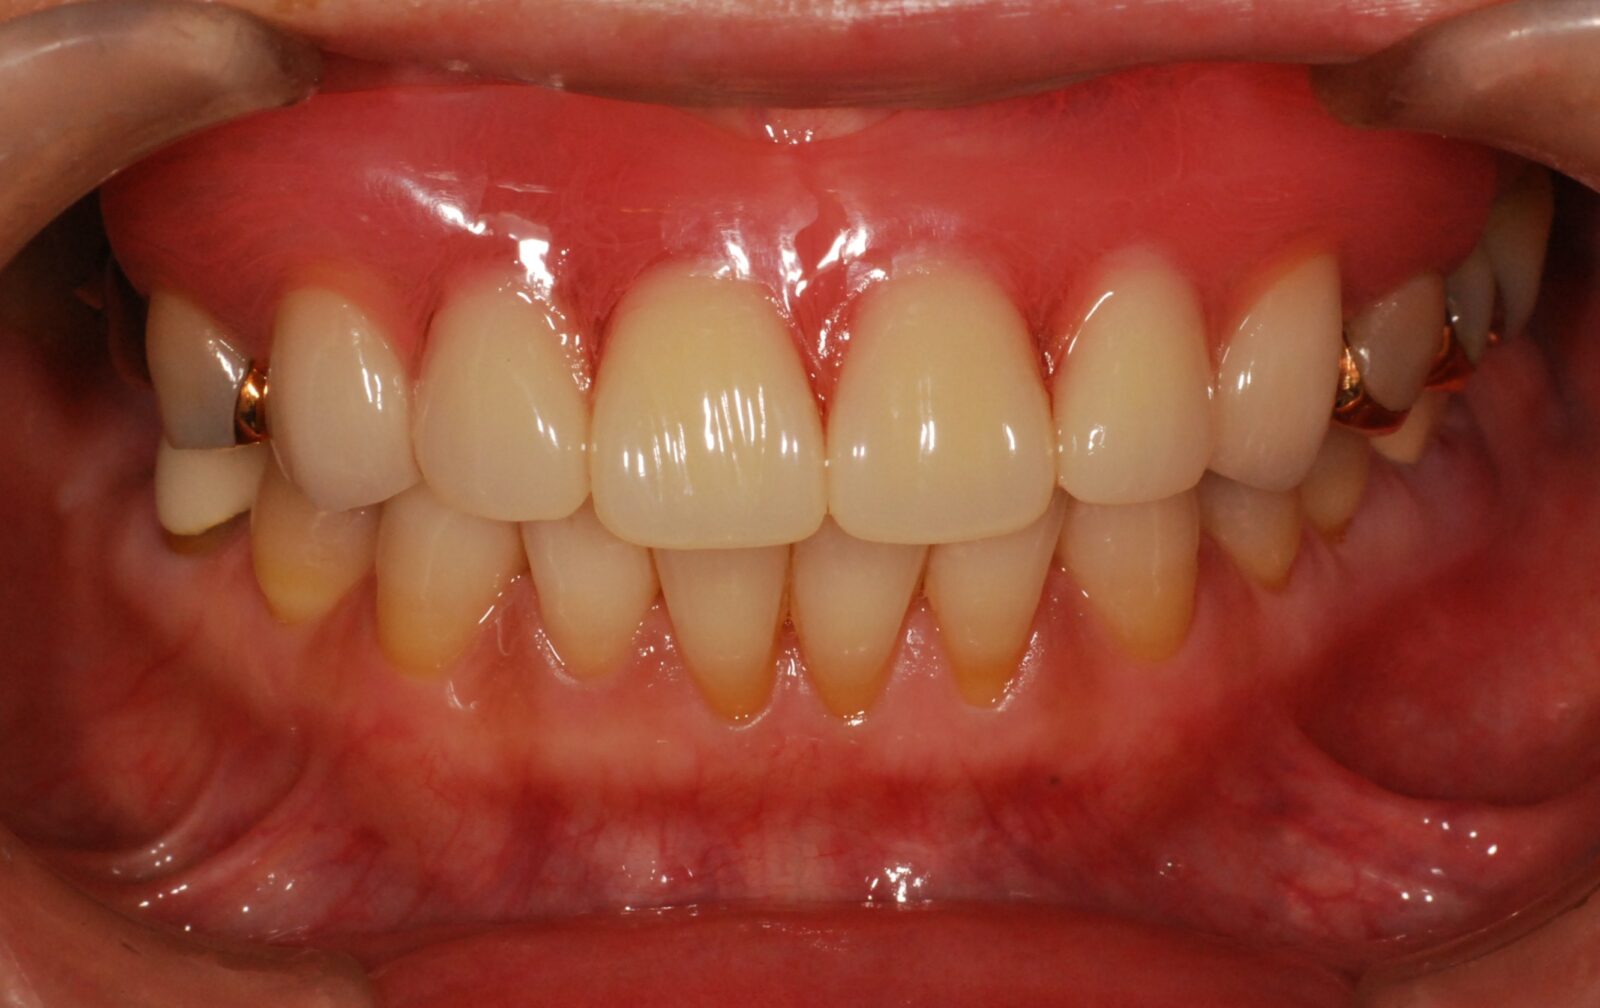

金属のバネが見えるのが嫌な方、もっとぴったりと密着した入れ歯を望まれる方にお勧めしているのが、右のように、金属のバネがない入れ歯「ノンクラスプ義歯」です。

金属バネ部分を、歯茎に近い色の樹脂で作ることで目立ちにくくしています。

当院では、「スマイルデンチャー」というノンクラスプ義歯を扱っています。

価格は約220,000円(税込)。ノンクラスプデンチャーを用いた症例。リスクとしては、過度の衝撃で割れることがあります。